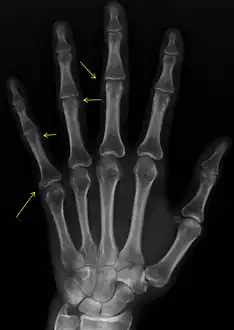

CREST syndrome (calcinosis and sclerodactyly)

CREST causes thickening and tightening of the skin with deposition of calcific nodules ("calcinosis").

Sclerodactyly

Though it is the most easily recognizable manifestation, it is not prominent in all patients. Thickening generally only involves the skin of the fingers distal to the metacarpophalangeal joints in CREST. Early in the course of the disease, the skin may appear edematous and inflamed. Eventually, dermal fibroblasts overproduce extracellular matrix leading to increased tissue collagen deposition in the skin. Collagen cross-linking then causes a progressive skin tightening. Digital ischemic ulcers commonly form on the distal fingers in 30–50% of patients.[3]